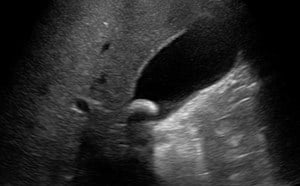

Effusion, Trauma, and Tamponade

• Pericardial effusions are common and range from benign to life threatening.

• In contrast to an effusion, epicardial fat pads are isolate to the anterior of the heart and often have increased echogenicity.

• In the setting of trauma, significant effusion may signify cardiac injury.

• The parasternal long axis view can be helpful in distinguishing between pericardial (anterior to descending thoracic aorta) and pleural (posterior to the DTA) effusions.

• Findings of tamponade on echocardiography include right ventricular diastolic collapse, right atrial systolic collapse, plethoric IVC, and increased inflow variation.19

• Pericardial tamponade is potentially lethal without intervention. Intuitively POCUS can decrease time to intervention although to date this is supported only by weak evidence.20

Video 9. Subxiphoid view of pericardial effusion with cardiac tamponade physiology. Note circumferential pericardial effusion, right ventricular diastolic collapse

• Epicardial fat pads are usually isolated to the anterior heart and have internal echoes. Pericardial fluid usually collects in the dependent posterior pericardial space and can be seen surrounding the myocardium anterior to the descending aorta. A left sided pleural effusion will be located posterior to the descending aorta.

• Image 15. Parasternal long axis showing pericardial effusion anterior to descending thoracic aorta.jpg

• Figure 15. Parasternal long axis showing pericardial effusion anterior to descending thoracic aorta

• Clotted blood in the pericardial space may have more hypoechoic appearance.

• Cardiac tamponade is a clinical diagnosis. Place the echocardiographic findings in the context of the patient’s clinical status.